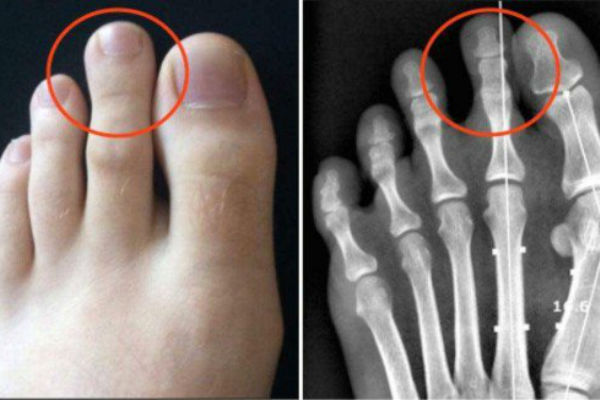

Ovo vam je sigurno privuklo pažnju, makar sa gledišta estetike! Radi se o tzv. Grčkom stopalu, pri kojem je drugi nožni prst duži od prvog i javlja se kod svega 14% stanovništva.

Iako nekim ljudima izgleda ružno i najradije bi željeli da ga nemaju, grčko stopalo obično je povezano sa snagom, inteligencijom i se*sipilom. S druge strane, postoje neke okolnosti koje bi trebalo uzeti u obzir

Grčko stopalo može donijeti probleme i uzrokovati bol, ukoliko se ne koristi adekvatna obuća.

Imajte na umu da, kada hodate ili trčite, vaše noge trpe većinu tjelesne težine, tako da je oblik stopala nešto što znatno utiče na cjelokupan osjećaj. Osobe sa grčkim stopalom češće trpe bolove u stopalima, a to je nešto što se ne smije ignorisati!